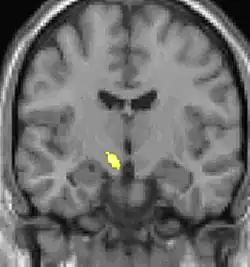

Positron emission tomography (PET) shows brain areas being activated during pain.

Positron emission tomography (PET) scans indicate the brain areas which are activated during attack only, compared to pain free periods. These pictures show brain areas that are active during pain in yellow/orange color (called "pain matrix"). The area in the center (in all three views) is activated only during cluster headaches. The bottom row voxel-based morphometry shows structural brain differences between individuals with and without CH; only a portion of the hypothalamus is different.[36]